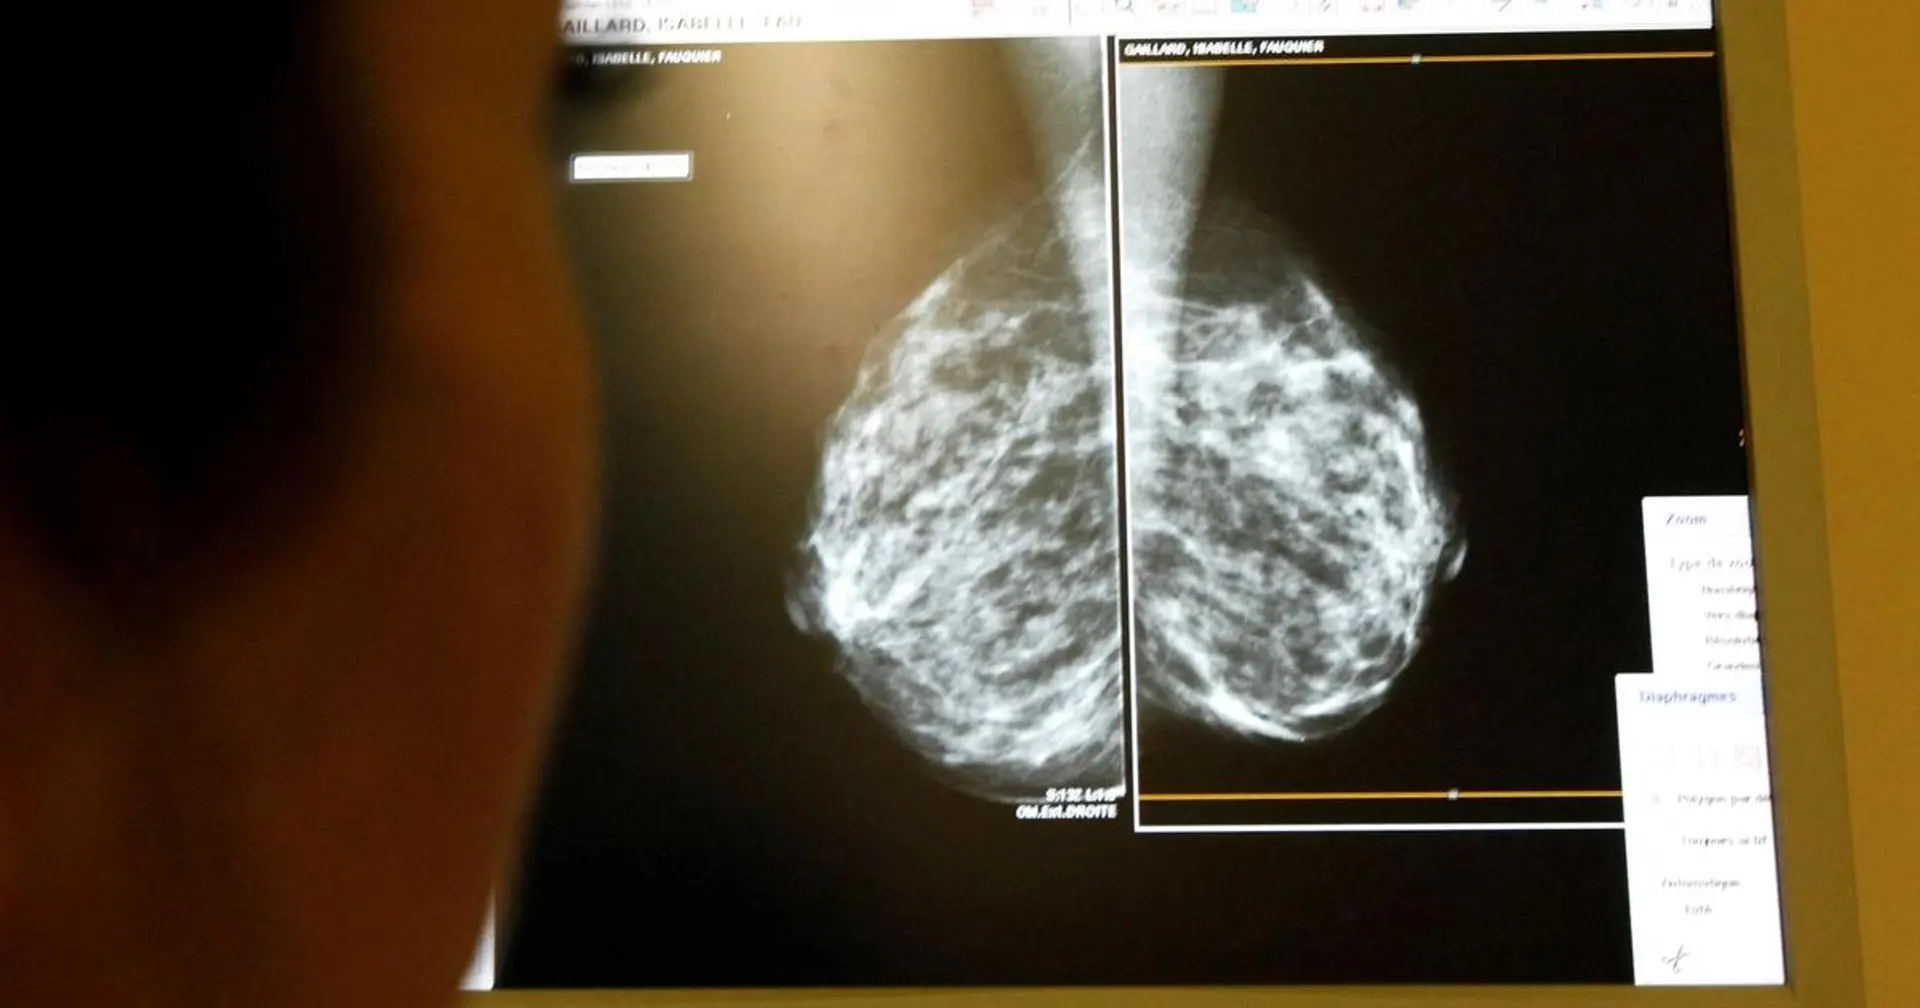

NYC Health + Hospitals CEO Mitchell H. Katz, MD, stated the system could replace many radiologists with AI, citing superior breast cancer detection and major cost savings. This offers health care procurement teams a clear mechanism for cost reduction, pending regulatory shifts.